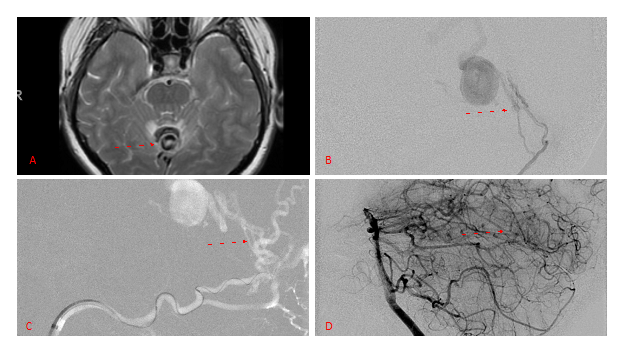

Embolization was successful at immediately reducing the pressure into the Aneurysmal Varix with greater than 90% reduction in A-V shunts. After an intensive period of critical care monitoring and care for her initial brain hemorrhage, she made a near complete recovery with mild intermittent left sided paresthesias and generalized deconditioning. After receiving inpatient and outpatient Acute Rehabilitation, Physical, and Occupational therapy, she completely recovered all of her Activities of Daily Living (ADLs) at 3 months and achieved an modified Rankin Scale (mRS) of 0. On follow-up angiography, small residual low flow A-V shunts were identified and targeted for Gamma Knife Radiosurgery (Figure 5 and 6).

Figure 5. Bilateral ECA Lateral angiograms (A and B) demonstrates small residual indirect supply To the AVM from the bilateral Occipital arteries.